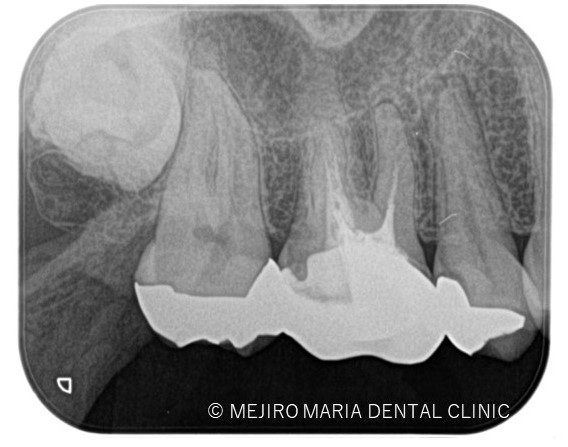

診査の結果、右上5番の歯髄には歯髄生活反応は確認できず、歯髄壊死が起因となる根尖性歯周炎と診断しました。術前のレントゲン診査により、根尖が2つに分岐していることを確認できます。

*赤丸で示しているところは、根が分岐している箇所を示す

今回は右上5番に対しての根管治療における、根尖3mmで分岐する根管へのアプローチでした。

当院のホームページでも記載があるように、根尖3mmは非常に複雑な形態をしていることから、根管治療でのアプローチの限界があるのも事実です。